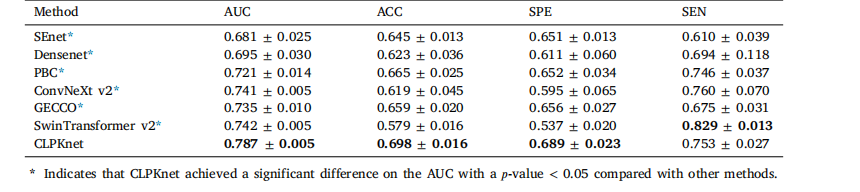

Table 7Prediction performance of our proposed method compared with that of other methods

表7 所提方法与其他方法的预测性能对比